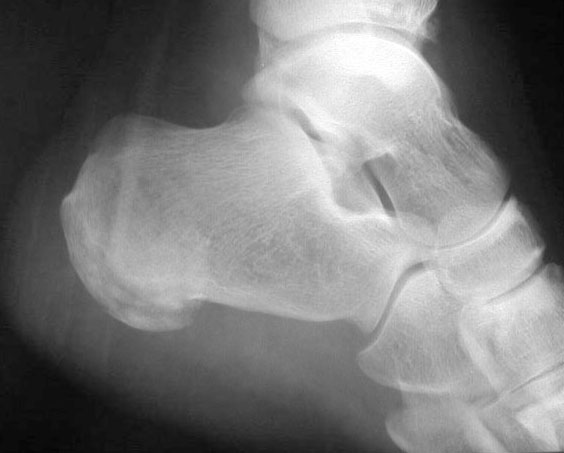

SIGNO DE LA ALMOHADILLA DEL TALÓN

El engrosamiento de los tejidos blandos del talón mayor de 23 mm es un signo de acromegalia, aunque no es específico, ya que también puede verse por obesidad, edema periférico, mixedema , traumatismo o infección del talón. La radiografía corresponde a un paciente con acromegalia.

Otro ejemplo del signo de la almohadilla grasa del talón en una fractura del calcáneo.

Referencias: Steinbach HL, Russell W. Measurement of the heel-pad as an aid to diagnosis of acromegaly. Radiology 1964; 82: 418-423. En: http://pubs.rsna.org/doi/abs/10.1148/82.3.418.

http://www.gentili.net/signs/12.htm.